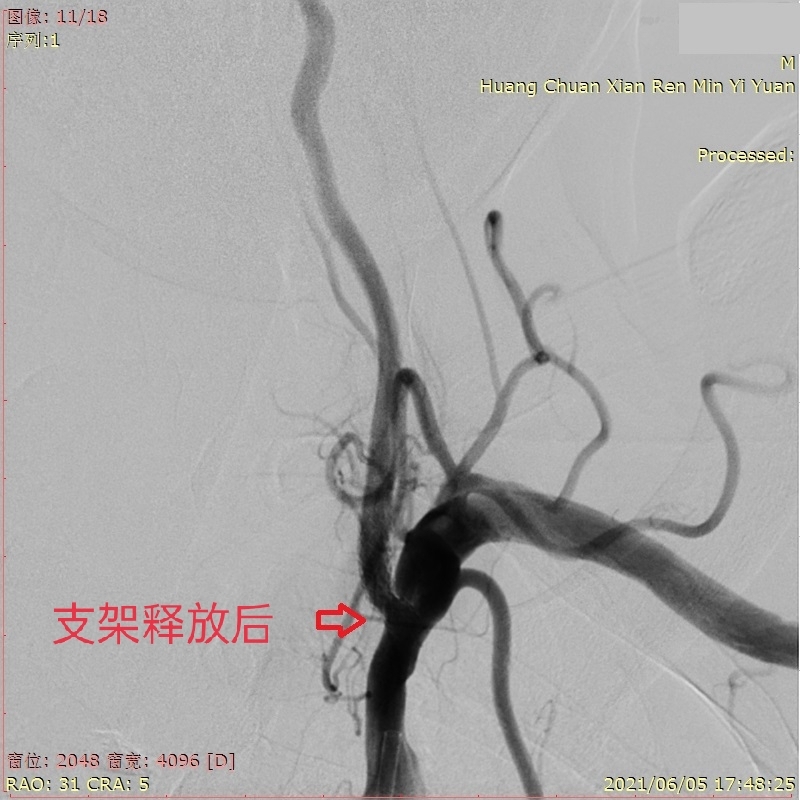

因为该手术在全县首例,其所用支架系统也是目前国内最新的雷帕霉素药物洗脱椎动脉支架系统,在全市也是首次应用,卒中团队专家们十分谨慎,病区主任张曙明、冯亮医师与患者家属进行有效沟通并获得家属同意后,于2021年6月5日,在院领导的支持下,在上级专家的指导下,神经内科、急诊医学科、医学影像科、介入手术室、手术麻醉科、重症医学科等全院多科室协调一致,积极配合,经过1个多小时紧张有序的手术,顺利将支架释放在潘大爷左侧椎动脉起始段狭窄处,血管修复情况良好。术后潘大爷症状明显改善,不久前出院时,潘大爷家属高兴地说这次手术成功不仅减轻了今后照顾患者的家庭负担,让潘大爷提高了生活质量,真是重获新生。